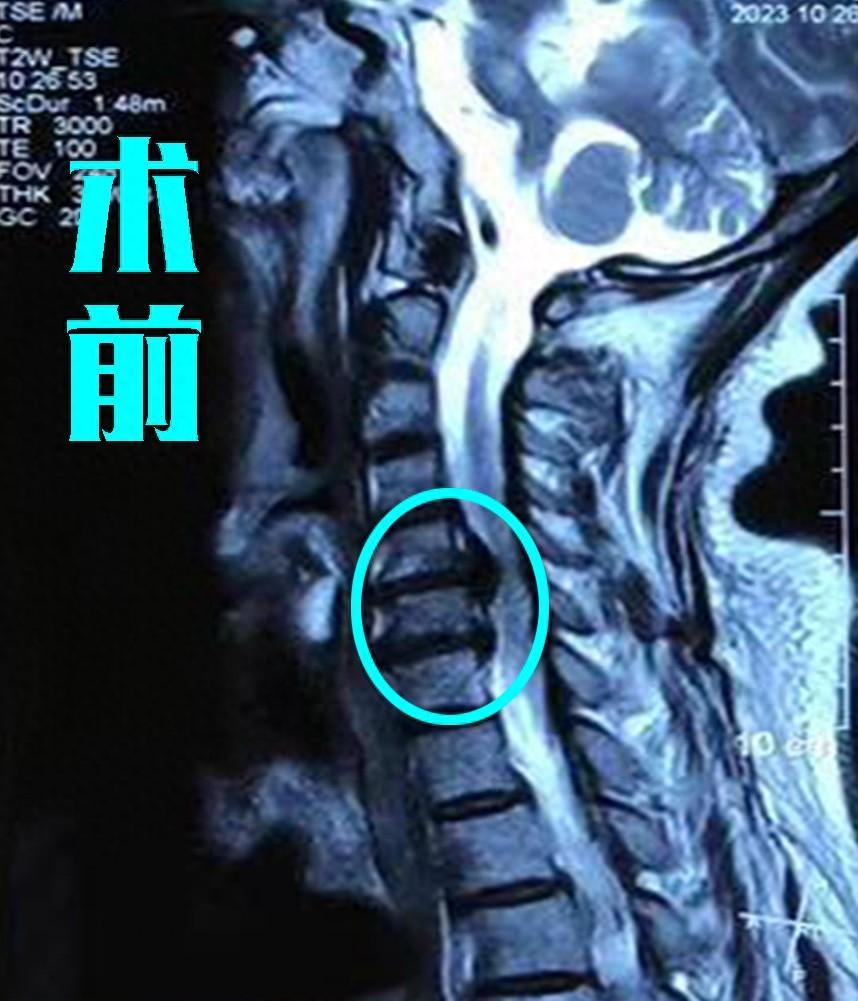

77岁颈椎间盘手术一例